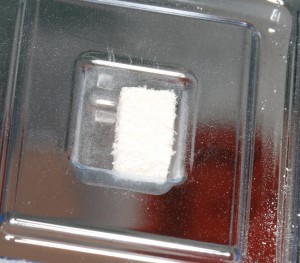

На мой взгляд, идеальный материал для аугментации лунки — это, все же Geistlich BioOss Collagen:

Несмотря на внешний вид и название, это НЕ КОЛЛАГЕНОВАЯ ГУБКА! Во многом, это действительно уникальный материал, а состоит он из 90% известного всем BioOss и 10% коллагена. Если сказать иначе — это BioOss, встроенный в коллагеновый каркас. И этим объясняются многие его свойства:

- легкая адаптация, он вполне себе режется скальпелем.

- не теряет форму при увлажнении, за счет коллагенового каркаса

- держит объем благодаря тому, что известный вам BioOss резорбируется крайне медленно.